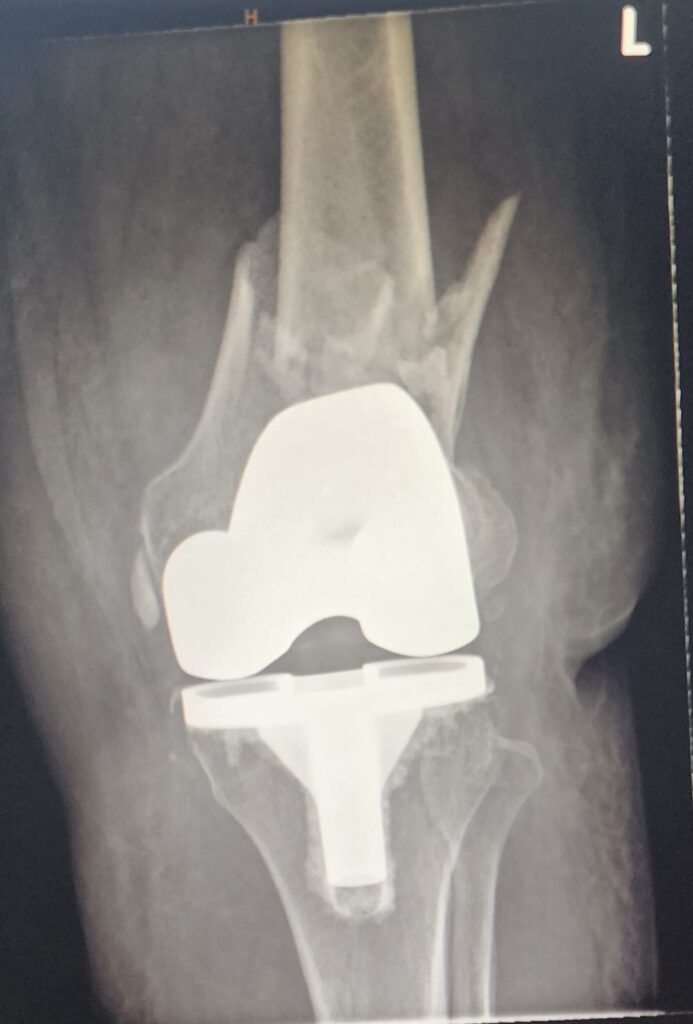

πŸ“Έ Intraoperative / Post-fixation X-rays

(Image 3 & 4) – Postoperative radiographs show the interlinked construct in place, providing optimal alignment and stability.

This technique allows immediate weight-bearing and controlled knee movement in a hinged brace.